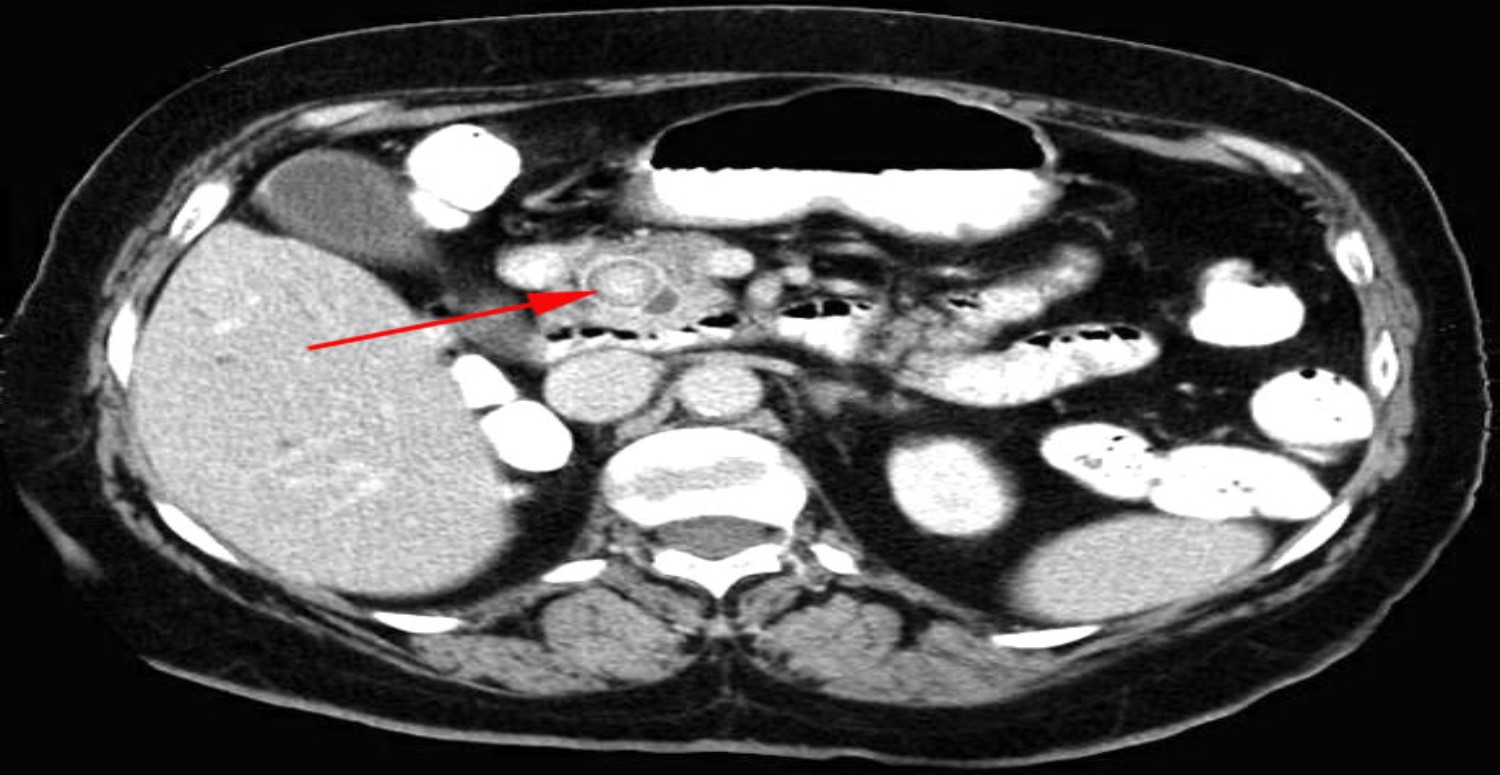

Safra kesesi taşlarının teşhisi için doktorunuz fizik muayene, kan testleri ve görüntüleme yöntemleri kullanabilir. Görüntüleme yöntemleri arasında ultrason, bilgisayarlı tomografi (BT), manyetik rezonans kolanjiyopankreatografi (MRCP) veya endoskopik retrograd kolanjiyopankreatografi (ERCP) gibi yöntemler bulunur. Bu yöntemler sayesinde safra kesesi ve safra yollarındaki taşların varlığı, sayısı, büyüklüğü ve yerleşimi belirlenebilir.